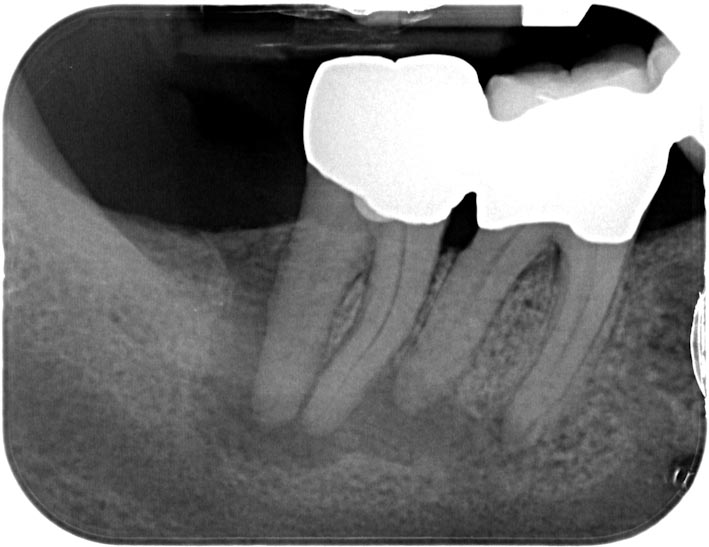

4746-1 Veröffentlicht 4. Juni 2013 am 709 × 547 in Recall Zähne 47 46 mit apikalen Aufhellungen Rö 47 46 vor Endo